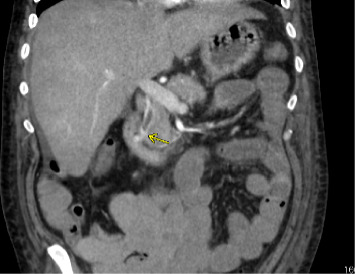

我们提出的情况下,49岁的男子入院急性肝功能衰竭合并血流动力学不稳定的胆道继发出血静脉曲张在胆管。由于静脉出血,放置全覆盖自膨胀裸金属支架(fcems)被认为是该患者肝动脉栓塞的最佳治疗选择。该手术的成功表明,fcems可以被认为是急性肝衰竭并发门静脉高压性胆道病并发血流动力学不稳定胆道患者肝移植的桥梁。

We present the case of a 49-year-old man admitted for acute liver failure complicated by hemodynamically unstable hemobilia secondary to bleeding varices in the bile duct. Placement of a fully covered self-expanding bare metal stent (FCSEMS) was considered the best treatment of choice over hepatic artery embolization in this patient because of the venous source of bleeding. The success of this procedure indicates that FCSEMS can be considered as a bridge to liver transplantation in patients with acute liver failure who develop hemodynamically unstable hemobilia secondary to portal hypertensive biliopathy.